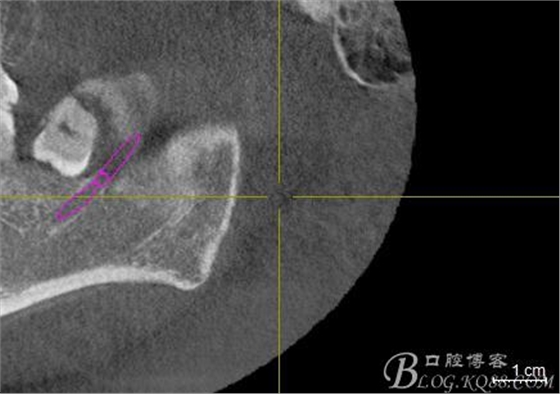

口內(nèi):38未萌出。37遠(yuǎn)中牙周袋10mm,CT:38牙冠倒置。牙齦紅腫,捫診可有少量血性滲出,無波動(dòng)感。印象診斷:38冠周炎。處理:1.抗炎治療,改善張口度。2.炎癥消退后,拔除38.

一、術(shù)前CBCT影像資料